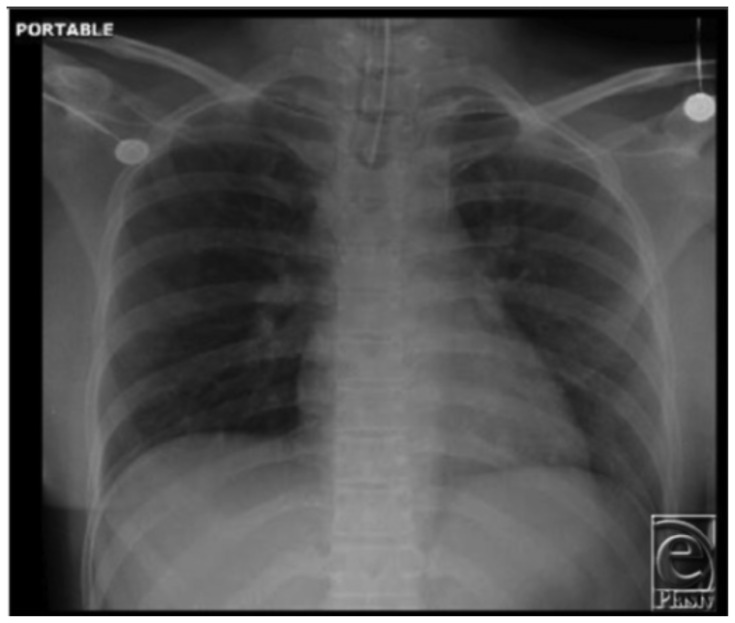

Abstract Image